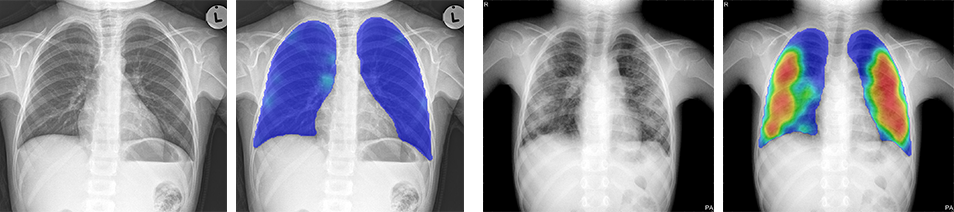

Figure 3. Two examples of chest radiographs of children both four years old. The left image is normal, and no abnormal regions are seen in the heatmap. The score of CAD4TB version 6 for this case is 22. The right image has clear abnormalities, accurately detected by CAD4TB 6. The image gets a score of 86.